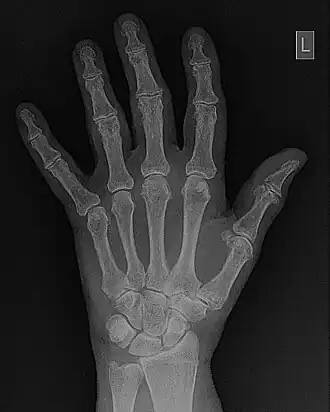

- An example of a Look-Up Table (LUT) which can be used for contrast enhancement is illustrated in Figure 5.5. The process is controlled typically by two controls on the console of the digital image processor - the Level and Window. It should be noted that variations in the names for these controls, and in their exact operation, can exist with different systems but the general approach described here is sufficient for our purposes. It is seen in the figure that the level controls the threshold value below which all pixels are displayed as black and the window controls a similar threshold value for a white output. The simultaneous use of the two controls allows the application of a gray-level window, of variable width, which can be placed anywhere along the gray scale. Subtle gray-level changes within images can therefore be enhanced so that they are displayed with greater clarity - see Figure 5.6.

- Fourier filtering is illustrated in more detail in Figure 5.10. The wrist/hand radiograph of the Figure 5.6 is again used for this illustration. You might remember that its 2D FFT was discussed in an earlier chapter. The filter is shown in panel (c) of the figure in the form of a two-dimensional image. It can be seen that the image data is symmetrical around the centre (i.e.isotropic) where its pixel values are relatively low. Outside this central dark region, a halo of bright pixel values dominates the image as the pixel value trails off slowly towards the periphery. An amplitude profile through this image is shown in panel (d) to further illustrate the effect. The filter can be used to modify the 2D-FFT by multiplying it by the filter values, for instance, to form a filtered 2D-FFT - as shown in panel (e). The Inverse FFT (IFT) of this data is then reveals the filtered image - see panel (f). Given that certain spatial frequencies have been amplified while others have been suppressed with this type of filter, it is called a Bandpass filter.